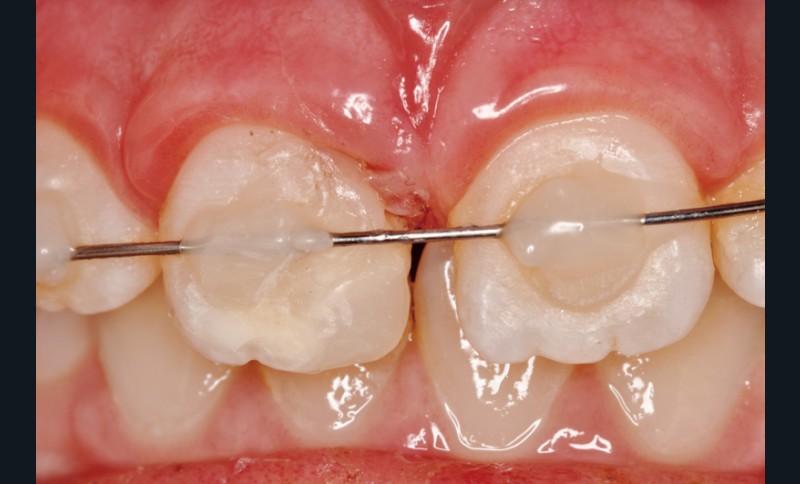

a à d Jeune patiente âgée de 8 ans, adressée suite à un traumatisme survenu 3 semaines auparavant, pour l’extraction de sa 21. La vue clinique montre un saignement ligamentaire, une mobilité coronaire et une fracture coronaire amélodentinaire longitudinale partant de l’angle mésial et se poursuivant en direction radiculaire sous-gingivale (a). Un test de vitalité positif indique que la dent est vitale, la radiographie permet de poser le diagnostic de fracture coronoradiculaire, et d’objectiver l’immaturité radiculaire (stade 8 de Nolla) (b). Une contention est mise en place et la plaie dentinaire coronaire est scellée au mieux par collage afin de limiter le risque d’une complication infectieuse (c). A 15 jours la dent est vivante et aucune complication n’est apparue (d). La patiente est revue après 3 mois pour déposer la contention, le test de vitalité est positif, et la radiographie de contrôle montre une apexogenèse en cours (e). Cependant la gencive s’est invaginée dans le trait de fracture (f). La zone est débridée sous microscope (g) puis scellée et reconstituée à l’aide d’un adhésif SAM et d’un composite fluide (h). Le contrôle radiographique à 6 mois est satisfaisant (i). Ce cas clinique illustre le fort potentiel des pulpes jeunes et du ligament alvéolodentaire à résister aux agressions et à assurer les fonctions dentinogénétiques et l’édification radiculaire.